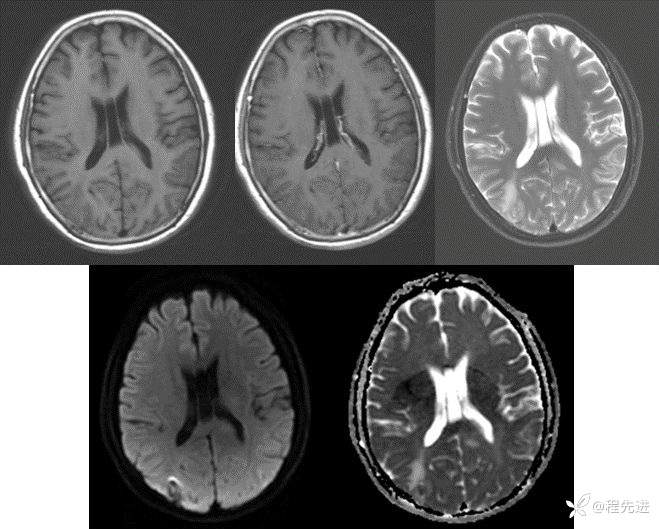

【患者信息】:女,65岁

【现病史及既往史】:间断头晕、头痛1月伴右手麻木2周。既往史:有左心房粘液瘤切除术

【检查】

CT:

MRI:

img